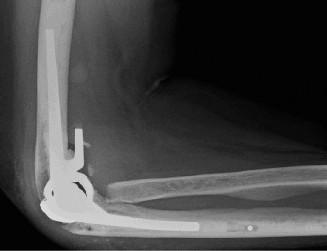

It should be noted that reverse total shoulder arthroplasty is also the procedure of choice in patients with cuff-tear arthropathy (aka rotator cuff arthropathy). Characteristics of cuff-tear arthropathy include superior migration of the humerus due to a massive rotator cuff tear, glenohumeral joint destruction, subchondral osteoporosis, and humeral head collapse (see Fig. 2–17). A reverse total shoulder

Figure 2–17_X-rays of a patient showing evidence of cuff tear arthropathy. The humerus is migrated superiorly, the glenohumeral joint is destroyed, there is subchondral osteoporosis, and the humeral head is collapsed. (From Ecklund KJ, Lee TQ, Tibone J, Gupta R. Rotator cuff tear arthropathy. _J Am Acad Orthop Surg. 2007;15(6):340–349.)